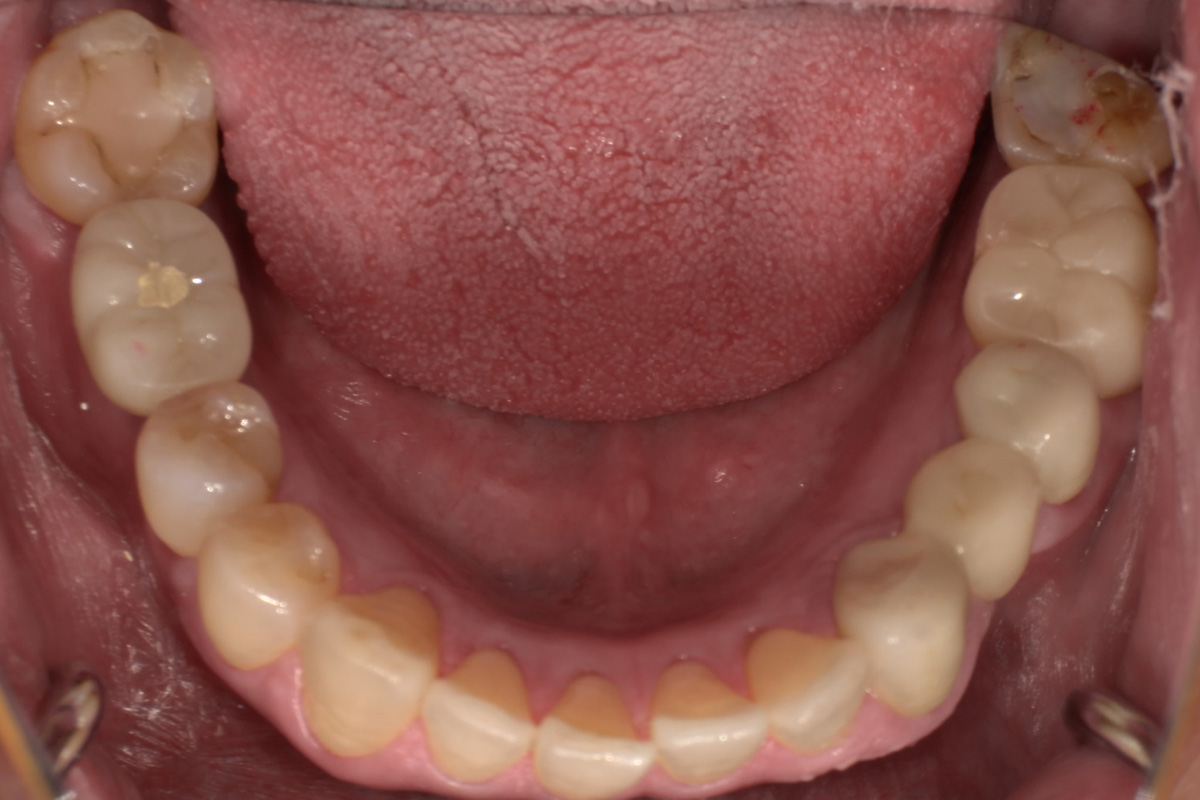

抜歯した箇所にインプラント治療を行った例

術前・術後の比較

初診時

歯が割れていて、痛みがあり、抜歯となりました。

レントゲン画像 治療前 インプラント治療後